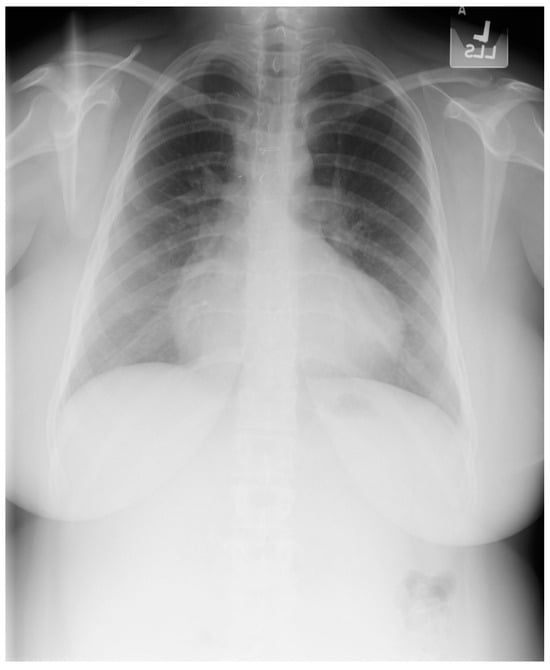

Figure 20.

Posteroanterior chest X-ray of Marfan syndrome: This 24-year-old female with Marfan syndrome had a chest X-ray because of her tall, thin stature and hyperextensible joints. She was asymptomatic. The image is well centered and the inspiration is good. Notice the widened upper posterior dorsal intercostal spaces. This indicates an increased dorsal kyphosis. The C-T ratio is normal. The ascending aorta, aortic arch and descending aorta are dilated. There was a faint decrescendo diastolic murmur of aortic regurgitation at the right upper sternal border. The normal heart size suggests that, in this asymptomatic woman, the aortic regurgitation was mild.